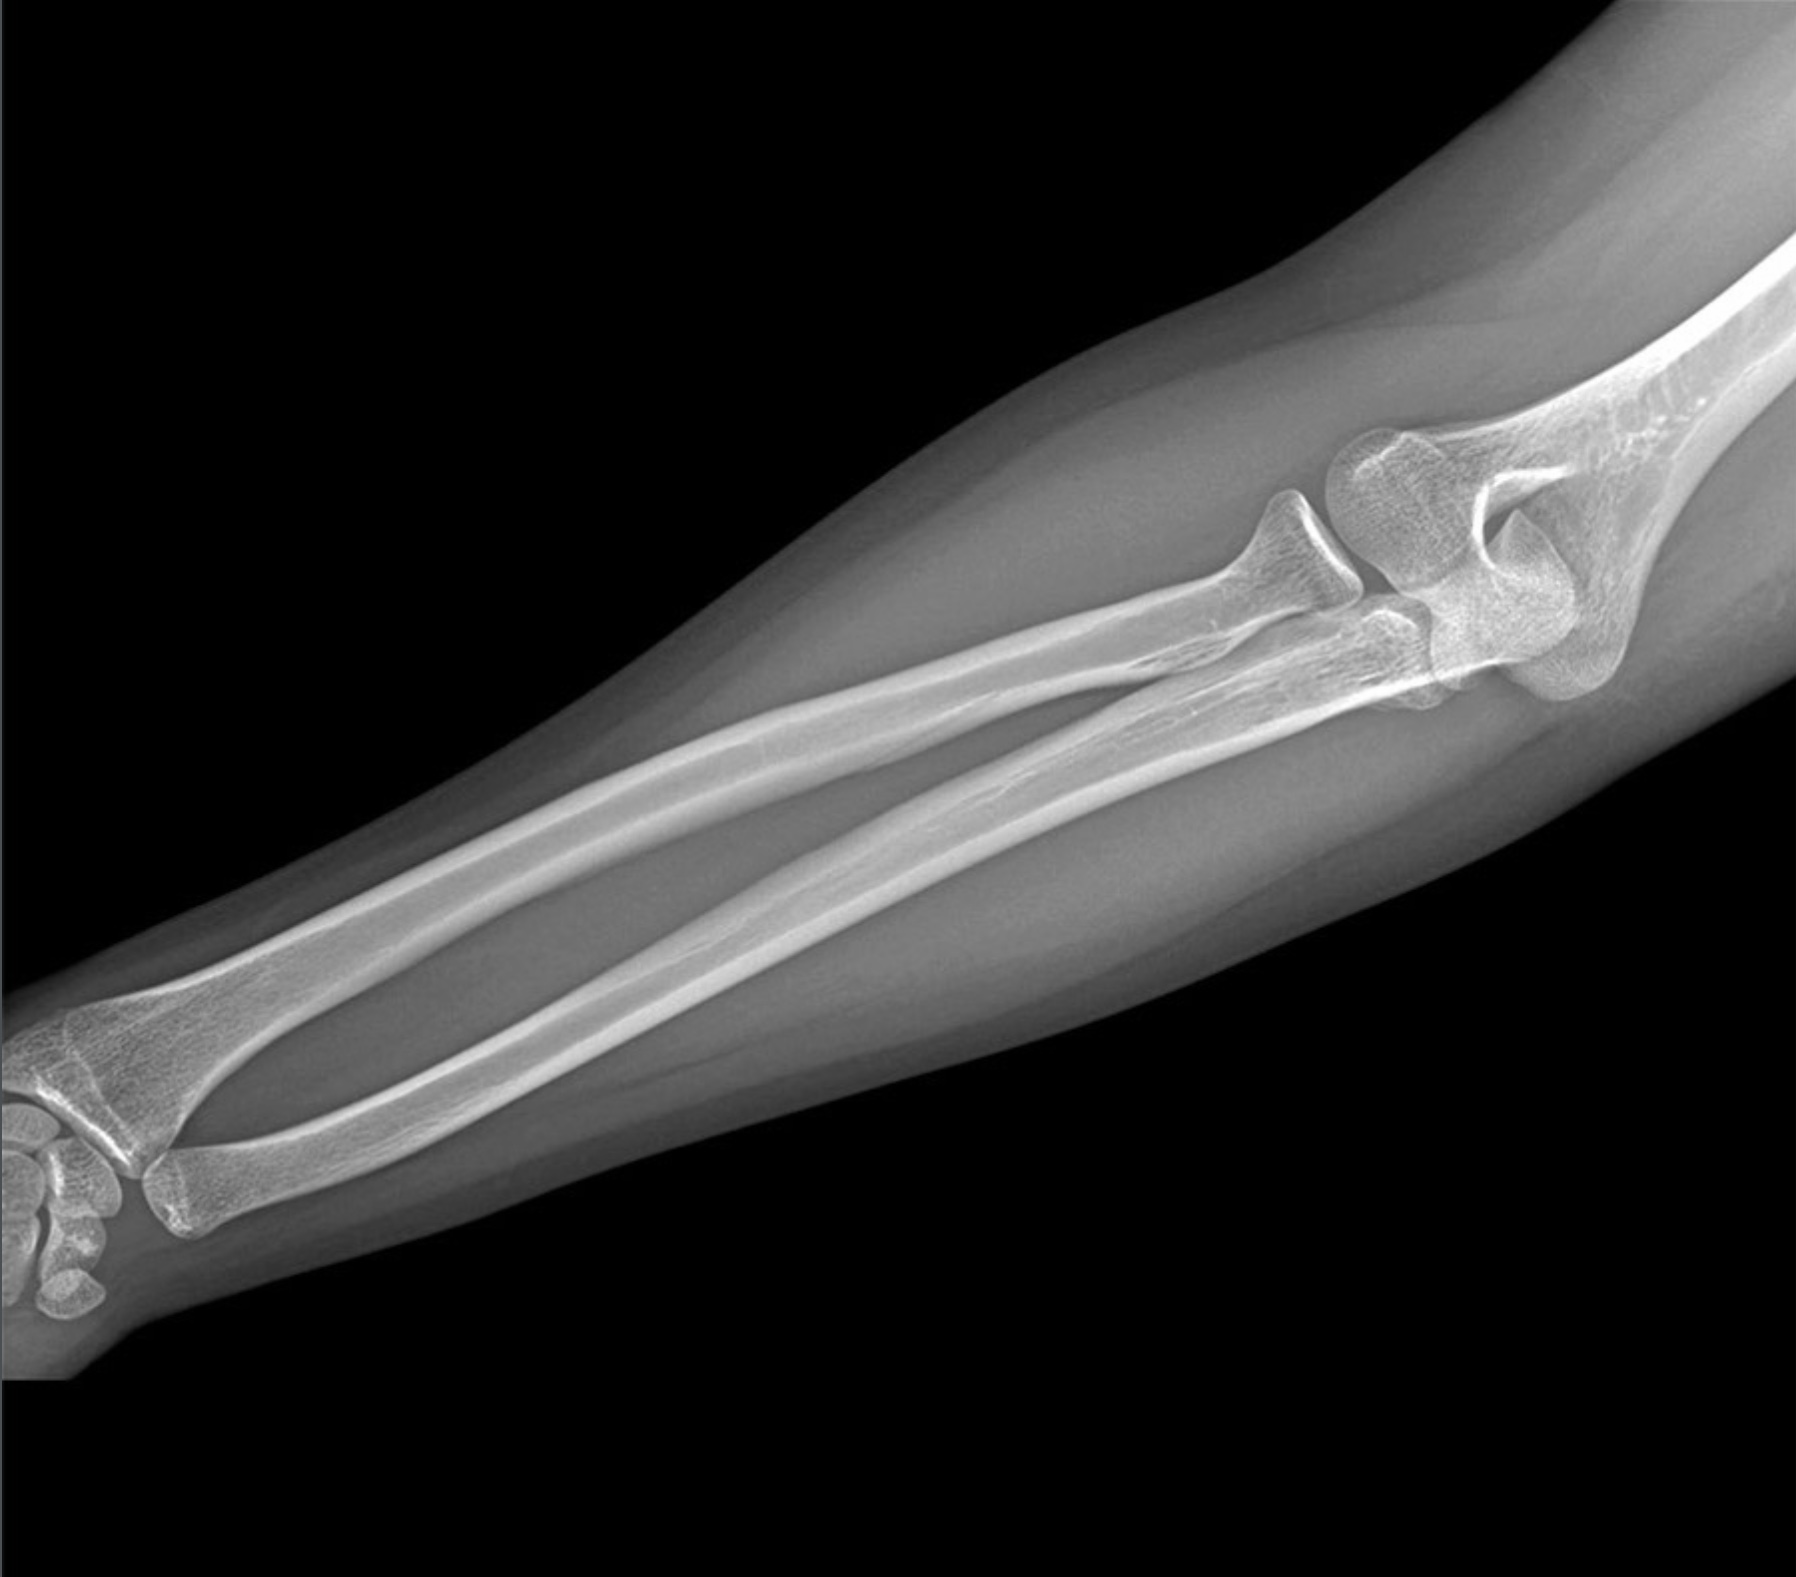

2. A 27-year old patient suffers a humeral shaft fracture at the radial groove. Discuss the anatomy of the posterior compartment of the arm, including boundaries, contents, musculature, vascular supply, innervation, lymphatics and relationships. Differentiate between motor deficits of posterior arm and posterior forearm musculature relative to branching of the radial nerve superior and inferior to the radial groove.